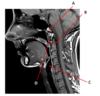

Which structure is labeled by E?

Cricoid cartilage

Which artery is labeled by B?

Maxillary artery

Which nerve runs in the carotid sheath in the middle of the neck?

Vagus nerve

Where in the neck does the common carotid artery split into the internal and external carotid arteries?

At the level of the upper border of the thyroid cartilage

(Around C3/C4)